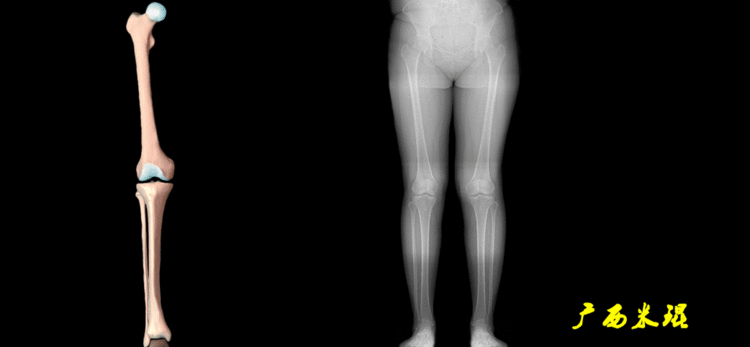

下肢力线及相关角度测量的前提是必须拍摄标准的站立位也就是负重位的下肢全长片。目前这样的照片都是放射科的技师在电脑上拼接出来的,大部分医院的DR都能够做到这一点。

无论如何,拍摄出来的下肢全长片必须包含髋关节中心、膝关节中心及踝关节中心,否则对临床是无用的。有了一张下肢的全长照片,我们需要确定下肢关节的中心点,通过中心点画出下肢的各种轴线,然后利用轴线与关节线的相交得出各种所需要的角度。

1、确定下肢关节的中心点(1)髋关节中心髋关节中心点由股骨头来确定,由于股骨头是相对比较规则的圆形,使用Mose圈或圆规就能确定股骨头中心也就是髋关节中心。

(2)膝关节中心膝关节中心点常用的有5个不同的定位方法,分别是股骨髁中点、股骨髁间窝顶点、膝关节间隙水平软组织中点、胫骨髁间嵴中点和胫骨平台中点,我们可以根据具体情况来选用。

(3)踝关节中心踝关节中心点常用的也有3个,分别是骨骼(内、外踝表面间距)中点、踝关节间隙水平软组织中点和距骨宽度中点。

2、画出下肢的轴线确定髋关节、膝关节、踝关节的中心点后,我们才能了解下肢的几个轴线。(1)解剖轴股骨和胫骨的骨干中线为解剖轴,股骨解剖轴和胫骨解剖轴的夹角正常值为174°±1°。

(2)机械轴机械轴是连接近端和远端关节中心点的直线。

机械轴要分前后位及侧位,站立前后位(也就是冠状面)股骨头中心与踝关节中心的连线通过膝关节中心,这是下肢的机械轴线,也就是下肢力线,常说Mikulicz线。冠状面的力线评估在临床工作中最常用、最基础、最重要。